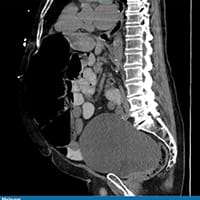

Todos os outros exames laboratoriais estão normais. É feita uma radiografia de abdome. O paciente é internado por causa dos seus exames. Uma tomografia computadorizada (TC) de abdome e pelve sem contraste é feita na sequência. Os achados dos exames de imagem são mostrados abaixo (Figuras 1 a 4).